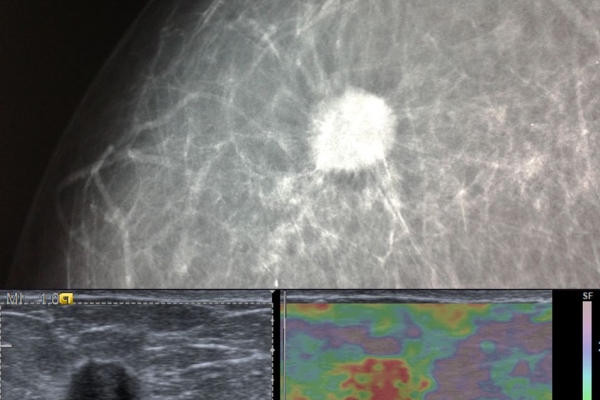

Η ελαστογραφία μαστού είναι μια σύγχρονη υπερηχογραφική μέθοδος που επιτρέπει τη διάκρισητων καλοήθων ογκιδίων από τους κακοήθεις όγκους.

Συνοπτικά ασκείται μια μικρή πίεση στους εντοπισμένους όγκους, μετρώντας την ελαστικότητα τους.

Ο καρκίνος γενικά εμφανίζει μεγαλύτερη σκληρότητα-ελαττωμένη ελαστικότητα σε σχέση με τα καλοήθη ογκίδια και επομένως η ελαστογραφία μπορεί να δώσει τις αναγκαίες πληροφορίες έτσι ώστε να μειώσει τις βιοψίες μαστού μόνο στις απολύτως απαραίτητες.